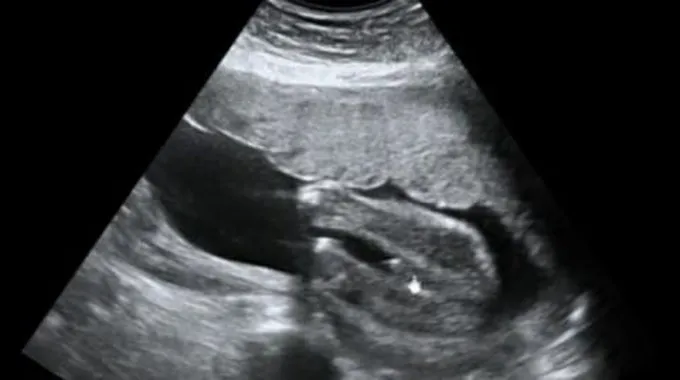

يُعدّ اختبار السونار (بالإنجليزية: Sonogram) أو ما يُعرَف بالتصوير بالموجات فوق الصوتيّة (بالإنجليزية: Ultrasound) أحد الاختبارات التصويريّة التي يتمّ القيام بها للحصول على صورة للجنين والأعضاء الداخليّة للأم الحامل مثل الرحم والمشيمة، ويوجد أنواع مختلفة من اختبارات السونار يتمّ إجراؤها بحسب مرحلة الحمل والسبب الرئيسيّ للتصوير، وتجدر الإشارة إلى أنّ الحاجة لإجراء هذا الاختبار تختلف من حالة إلى أخرى، حيثُ إنّ بعض حالات الحمل الطبيعيّة لا تحتاج إلّا لعدد محدود من التصوير بالموجات فوق الصوتيّة، بينما قد تحتاج بعض حالات الحمل الأخرى لإجراء عدد أكبر من اختبارات التصوير في حال الشك بوجود مشكلة صحيّة أو الإصابة بأحد من مضاعفات الحمل.[1]

منذ لحظة إخصاب البويضة بالحيوان المنويّ يتحدّد نوع أو جنس الجنين، بالإضافة إلى جميع الصفات الجينيّة والوراثيّة الأخرى له، كما تبدأ الأعضاء التناسليّة بالتشكّل منذ الأسبوع السادس من الحمل، وعلى الرغم من ذلك فإنّ الطبيب قد لا يكون قادراً على معرفة نوع الجنين حتى الوصول إلى منتصف الحمل تقريباً، ويمكن التعرّف على نوع الجنين في بعض الحالات منذ الأسبوع السادس عشر من الحمل، أو قد يحتاج الطبيب إلى عدّة أسابيع أخرى بناءً على موقع الجنين في الرحم، ولكن في معظم الحالات يكون الطبيب قادراً على الكشف عن نوع الجنين بحلول الأسبوع الثامن عشر من الحمل تقريباً،[2][3] وتعتمد دقّة تحديد نوع الجنين على العديد من العوامل المختلفة، مثل نوع الجهاز المستخدم، وعُمُر الجنين، وتجدر الإشارة إلى وجود عدد من العلامات التي يعتمد عليها الطبيب في الكشف عن نوع الجنين، نذكر منها الآتي:[4]